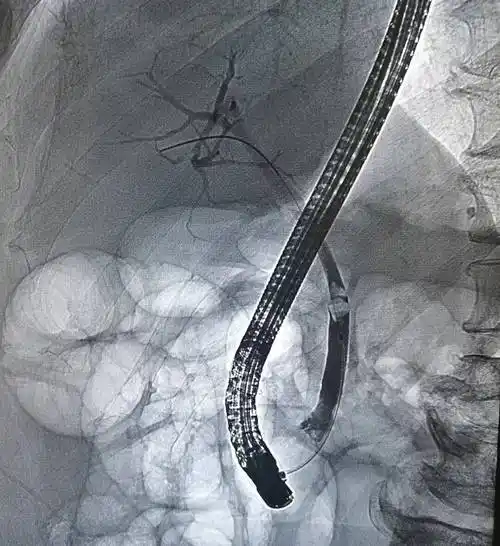

胶州:"三镜"联合手术,"巧取"胆结石

20分钟精准取石!冠县人民医院消化内科ercp技术再攀高峰

取石术,不开刀为胆总管结石患者成功取石

胆道胰腺疾病微创治疗的利器"ercp",您了解吗?

93岁婆婆胆管结石引发高烧腹痛"警报",医生妙用微创ercp技术"精准拆弹